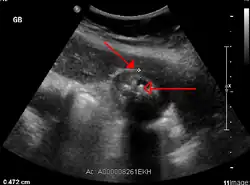

Right upper quadrant abdominal ultrasound is most commonly used to diagnose cholecystitis.[1][25][26] Ultrasound findings suggestive of acute cholecystitis include gallstones, pericholecystic fluid (fluid surrounding the gallbladder), gallbladder wall thickening (wall thickness over 3 mm),[27] dilation of the bile duct, and sonographic Murphy's sign.[13] Given its higher sensitivity, hepatic iminodiacetic acid (HIDA) scan can be used if ultrasound is not diagnostic.[13][14] CT scan may also be used if complications such as perforation or gangrene are suspected.[14]

Acute cholecystitis as seen on ultrasound. The closed arrow points to gallbladder wall thickening. Open arrow points to stones in the GB